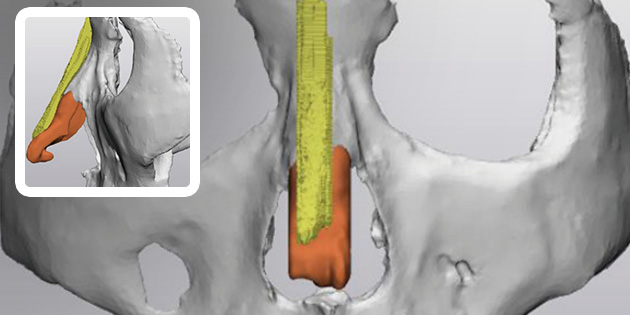

This is 1:1 customized rhinoplasty that allows you to create the most suitable implant for your nose by using 3D printer to create the patient’s skeleton, cartilage, skin tissue, and muscle with data obtained from 3D-ct images.

Because it is possible to manufacture a customized implant that fits perfectly to the nasal bone, it is safe and there is little worry about reoperation as it significantly reduces side effects such as bending, silicone seepage, and lifting.

4Custom Nose Implant

A custom-designed, custom-made nose implant for patients is made with a 3D printer.